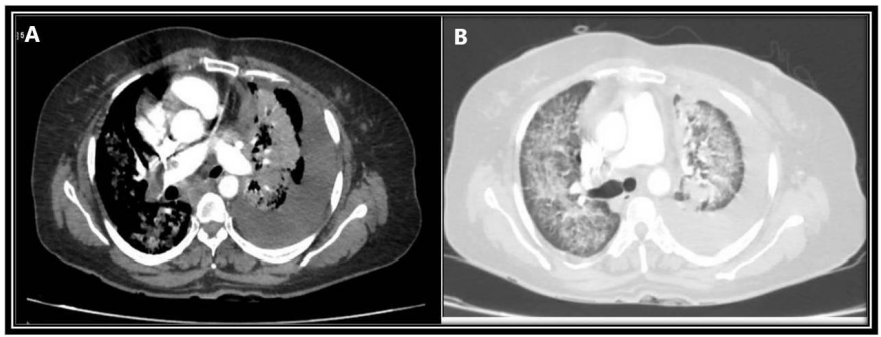

A 40 year non smoker female with no known comorbidities who had complaints of dry cough for 10 days, and breathlessness for 1 month, presented to us with sudden onset worsening of breathlessness. Her heart rate was 150bpm, blood pressure 80/60mmHg, Sp02 75% and respiratory rate 30/min. ECG showed sinus tachycardia. Chest radiograph was suggestive of left massive pleural effusion. Diagnostic and therapeutic pleural tapping was done, but breathlessness persisted. Her blood investigations showed elevated D-dimer levels. We then performed computed tomography pulmonary angiography (CTPA) which showed filling defect in right distal main pulmonary artery extending into right upper lobar and inter lobar artery (Figure 1A). Bilateral peribronchovascular consolidation, predominantly in left upper lobe, left paraesophageal nodal mass and left moderate pleural effusion was also noted (Figure 1B). In addition to the respiratory and hemodynamic support, she was thrombolysed with intravenous streptokinase (250 000 IU as a loading dose over 30 min, followed by 100 000 IU/h over 24 h), after ruling out any contraindications to thrombolysis. She was continued on therapeutic anticoagulation. Pleural fluid cytological and cell block evaluation was suggestive of adenocarcinoma primary lung and was negative for EGFR, ALK and ROS1 (Figure 2). Her whole-body positron emission tomography (PET) and contrast enhanced magnetic resonance imaging (CE-MRI) brain did not show any additional foci of metastasis. A diagnosis of stage IVA adenocarcinoma lung was made. She was started on chemotherapy and was duly discharged on non-vitamin K antagonist oral anticoagulants (NOACs).

Figure 1 A. CTPA showing filling defect in right distal main pulmonary artery extending into right upper lobar and inter lobar artery.

B. Lung window showing bilateral peribronchovascular consolidation, predominantly in left upper lobe, and left moderate pleural effusion.